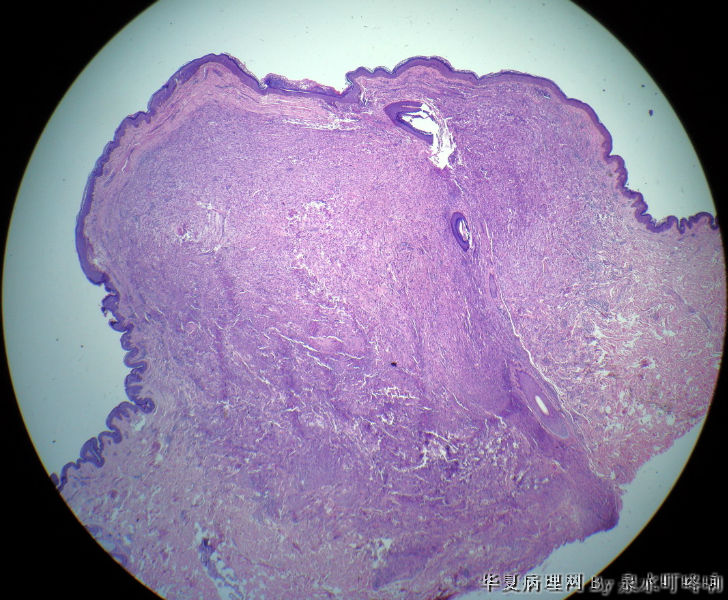

• 颈后部肿物图3

图3

考虑神经来源肿瘤,需要些免疫组化标记啊,还请其他老师指导

考虑纤维组织细胞瘤,建议标记一下

考虑:1:神经鞘  2:纤维组织细胞瘤。建议免疫组化鉴别。做哪些免疫组化哪?

北京肿瘤医院会诊:纤维组织细胞瘤。